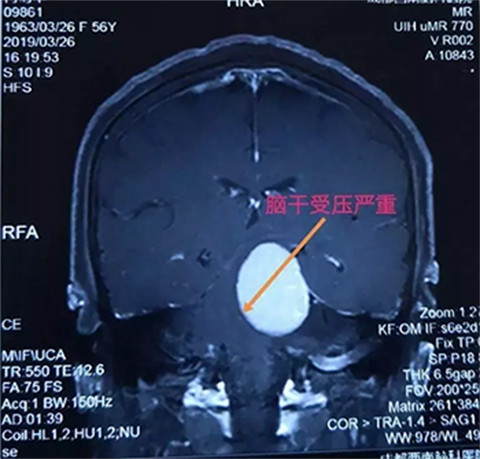

腦腫瘤磁共振影像